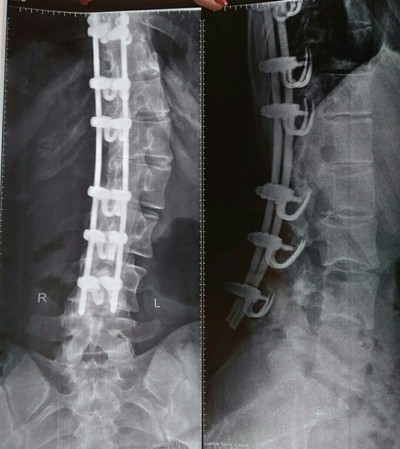

История 1. Еще один свежий сколиоз

Парень, 16 лет, геймер. S-образный сколиоз: в грудном отделе позвоночника 4 степени, в поясничном отделе позвоночника 3 степени. Дистрофические изменения тел грудных позвонков.